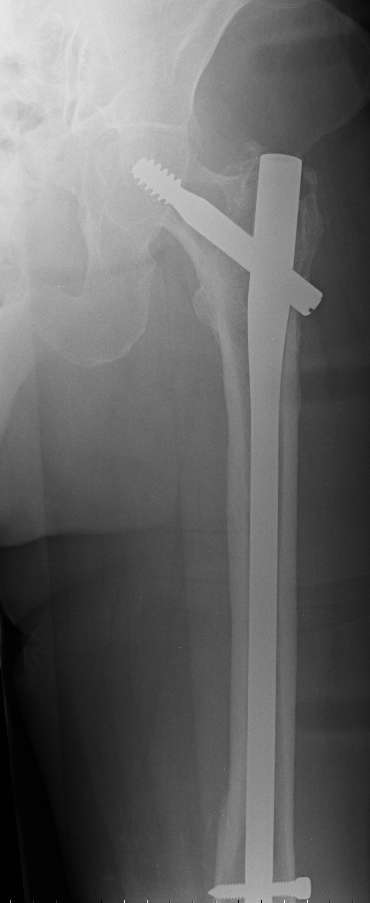

- It is an long, spiral, metaphyseal fracture – very good chance of healing (will not be any need for any bone cement…bone substitute – filler)

- I would use: distal femoral locking plate with few cerclage wires in midsegment and some unicortical locked screws and cerclage wires proximal…

I would consider retrograde femoral interlocking nail after Gamma nail removal during the same surgery.

In my opinion the femoral bone looks osteoporotic, but no bone defect is visible to justify bone cement.

If we have a ready entry point after the gamma removal why perforate the intact knee for another entry - why not just insert a longer antegrade

nail? We definitely would do this. Of course retrograde nailing as well as locked plating would do the job but antegrade nailing in this case is

least invasive among mentioned options.

4. We could treat this fracture like there is no a nail - new locking plates allow for secure fixation.... two similar cases are attached...

Images sent by Professor Kanlic look nice, very good job. Excellent achorage in distal fragment. However, unicortical screwing or bicortical

makes a difference, also for locked screws. Proximal fragment unicortical fixation may present stability not easlily predictable. Certainly its stability for wheelchair should be sufficient. Full weight bearing can not be mentioned for this case. If minimal bearing is allowed full weight

single step may happen in elderly.

Gamma nail exchange may probably fit the criteria of optimal and minimal invasivness, indeed. Removal could be relatively fast due to large intramedullary diameter seen on X-ray.

I do agree that distal locking of the nail in distal femur remains critical.

Dear Sir, in my opinion it's better to take off the gamma nail, anatomically reduce the spiral with 2 lag screws, and fix the shaft fracture with a LISS-LCP 13 holes. No bone graft. Immediate mobilization and weight bearing.